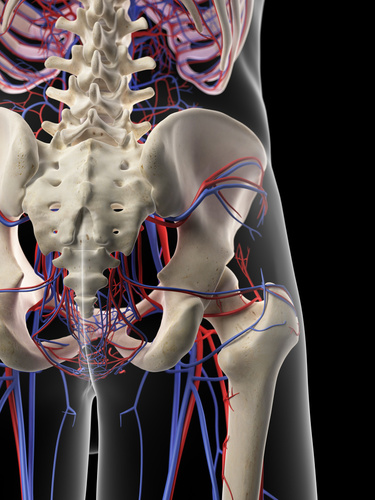

ガチガチの大殿筋を3秒で“ふにゃふにゃ”に

腰痛を撲滅する上殿動脈リリース

- ガチガチの大殿筋を緩めるのに、グリグリマッサージする事しか出来ない。

- 大殿筋をリリースしていっても最後の硬結が取り切れない。

- 大殿筋をリリースしていってもすぐに戻ってしまう。

もしあなたがこんな悩みを持っているならこのテクニックは必須です。

このテクニックをマスターする事で、あなたがいつも使っている大殿筋のリリーステクニックは不要となります。それほどの威力を持ったテクニックをあなたに公開します。

これを見ることで、大殿筋を上殿動脈を使いリリースする方法を学ぶ事が出来ます。さらに下肢血流量までをも同時に改善し、冷え性やむくみまでをも瞬時に改善する事が出来るようになります。

あなたがいつまでも大殿筋をグリグリマッサージしているのなら、この上殿動脈リリースを使ってみて下さい。